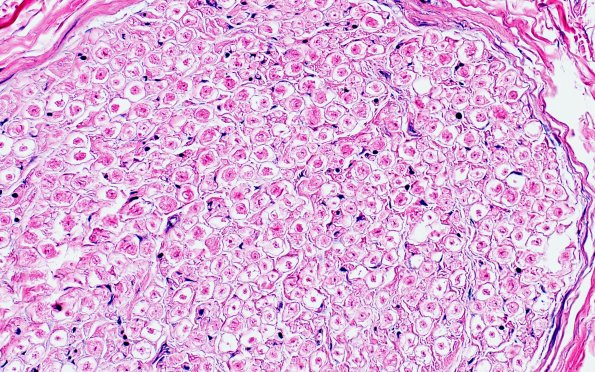

17C3 Artifact, vesicular myelin, 6 days unfixed on wet gauze H&E 40X 1

Higher magnification of image #17C1 (H&E)